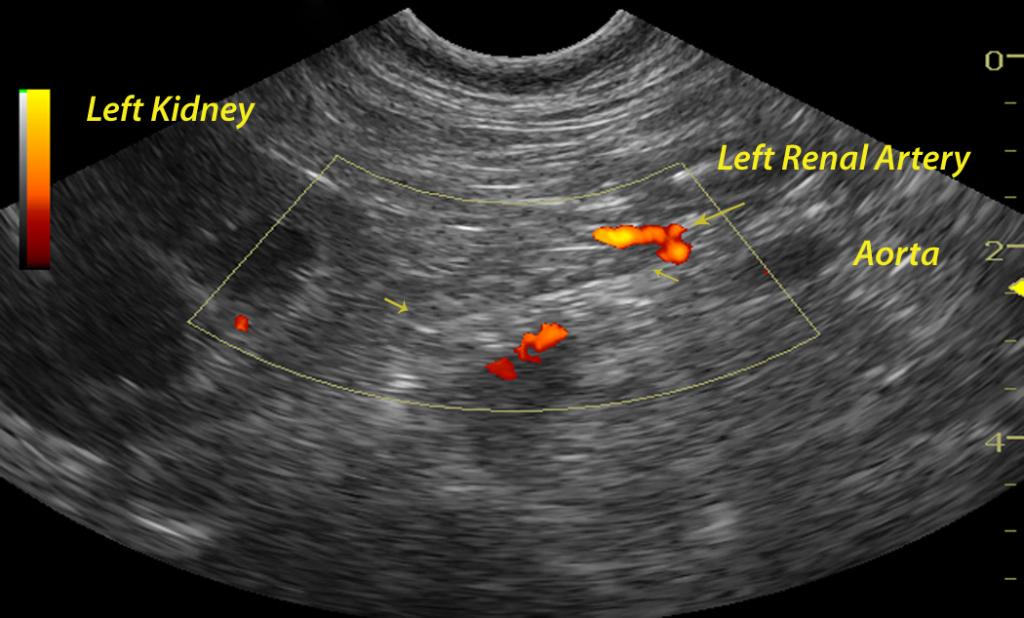

An 8-year-old FS Basset Hound dog was presented for crying throughout the night and vomiting food, fluid, and mucous. On physical examination, she was found to have pink mucous membranes and a normal body temperature. She had bilateral conjunctivitis as well as a bilateral otitis externa (Malassezia). No abnormalities were noted on auscultation of her heart and lungs. The patient was treated symptomatically as an outpatient with anti-emetics and gastroprotectants. Six days later, the dog returned as she was depressed and lethargic. She was in lateral recumbency upon presentation and she was hypothermic with pale pink, tacky and cold mucous membranes. She was admitted to the hospital for I.V. fluid therapy and blood work. The serum biochemical profile revealed elevated ALT, elevated AST, and elevated GGT, azotemia, hyperproteinemia, hyperalbuminemia, hyperglobulinemia, hyperbilirubinemia, hyperkalemia, hypercalcemia, hyperphosphatemia, hypermagnesemia, hyperamylasemia, and an elevated CK. The CBC showed an elevated hemoglobin and leukocytosis consisting of a monocytosis and eosinophilia.